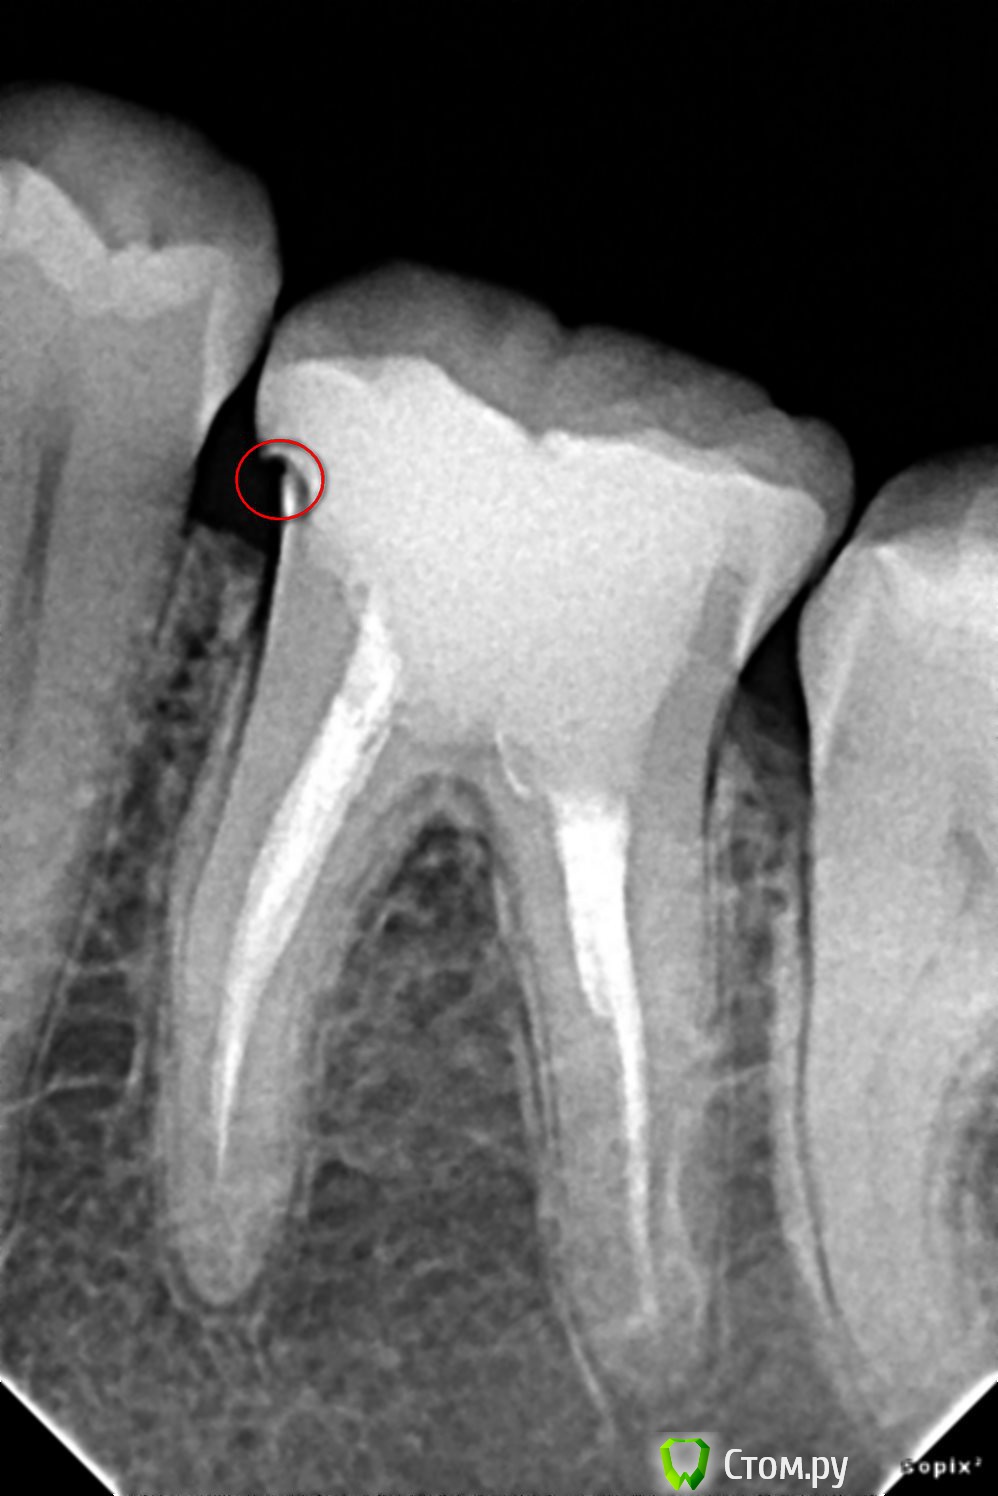

ТатьянаС Опубликовано 3 ноября, 2014 Поделиться Опубликовано 3 ноября, 2014 Добрый день! Недавно мне поставили керамическую вкладку на 6 нижний зуб слева, по итогам сделали снимок, он во вложении, настораживает меня место, обведенное красным. Врач говорит, что т.к. пища туда не попадает, все ок и ничего делать не надо. Как считаете я зря переживаю или нет? Спасибо! Ссылка на комментарий

IvanK Опубликовано 3 ноября, 2014 Поделиться Опубликовано 3 ноября, 2014 Здравствуйте Нужно переделать 1 Ссылка на комментарий

SDC Опубликовано 3 ноября, 2014 Поделиться Опубликовано 3 ноября, 2014 Спасибо за ответ, переделать - вытащить вкладку и сделать все заново? Или можно это место как-то обточить?Переделать. Не откорректировать, а переделать 2 Ссылка на комментарий

IvanK Опубликовано 3 ноября, 2014 Поделиться Опубликовано 3 ноября, 2014 Возможно, имеет смысл задуматься о коронке 2 Ссылка на комментарий